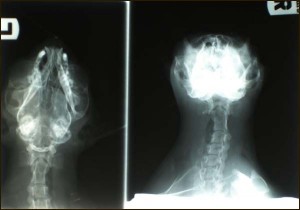

Kocourek Křižík. Jeho vyšetření je možné pouze v narkoze. Jakmile usnul, byl prohlédnut celkově, pak jeho problémové ucho, které v prostoru před bubínkem zcela vyplňují polypy. Byla mu odebrána krev a veterinářka udělala dva rentgenové snímky hlavy. Všechna tato vyšetření mají zjistit stav jeho ucha a to, zda je Křižík ve svém věku schopen těžké operace. Výsledky krve budou ve čtvrtek večer.

závěrem rentgenový snímek hlavy

Podle dnešního telefonátu, jsou výsledky krve a rentgeny Křižíka v pořádku, je tedy schopen operace. Bude provedena resekce ucha jako u Modřiny. Termín operace zatím nemáme, musí být teprve dohodnut. Rizika operace: 1/ absces a další operace 2/ ochrnutí části tváře na straně postiženého ucha. Pokud operaci neprovedeme: 1/ absces a jeho prasknutí, pak operace a plastika a stejná rizika jako v případě plánované operace 2/ stálá bolest, zánět a výtok z ucha 3/ závažné neurologické problémy.